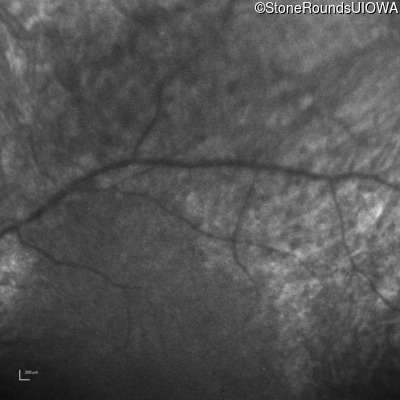

Infrared Fundus Photograph - Right -

No Light Perception

Exemplar

Expanded OCT Stack

×